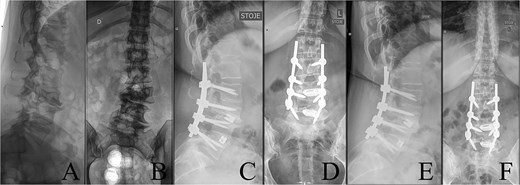

Preoperative CT demonstrating L3 hemivertebra; anteroposterior view (A) on the left side of the image, and lateral view (L) on the right side of the image.

A 43-year-old female with a history of a previous isolated right-sided L3 foraminotomy at an external facility (this intervention temporarily alleviated her leg pain but exacerbated her back pain) was referred to our institution due to chronic back pain, right-sided leg pain without neurological dysfunction, and a forward-leaning posture, which was correctable with verbal cues. The back pain, in the absence of neurological deficits, began 13 years prior, at which time she was diagnosed with adult congenital scoliosis caused by L3 hemivertebrae (Figs 1 and 2). Imaging confirmed a L3 hemivertebra resulting in a 24° Cobb angle of congenital scoliosis (Fig. 1), without associated cord abnormalities on MRI.